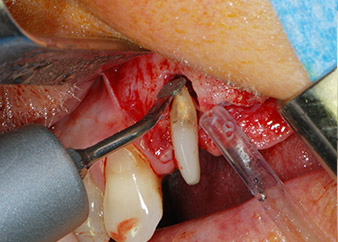

След един месец, в деня на операцията, болката и възпалението в зъб 24 е минимално, но подвижността в Miller class 2 е на лице. След отваряне на ламбата и почистването на периапикалната и перирадикуларната тъкани, обхватът на костния дефект стана очевиден (Фиг. 2 и 3).

В букалния корен, цялата вестибуларна и дистална кост липсва. Захващането е значително ограничено до палатиналния корен, подчертавайки предварително лошата прогноза. Зъб 27 също откри намалено хоризонтално захващане и минимално апикално разреждане (Фиг. 1) без клинични симптоми.

Въпреки това, ние се придържахме към първоначалния си план да запазим и двата зъба като абатмънти за временен мост по време на 6-месечната остеоинтеграция на имплантите. При повторна интервенция, ситуацията трябва да се преразгледа. Първо, в опит да се овладее ендо-перио проблема, останалата повърхност на зъба е внимателно обработена с пиезохирургично оборудване (Piezomed, W&H, използван с накрайник S1 под формата на шпатула, първоначално проектиран за ерозия на латералната синусна стена) (Фиг. 4).